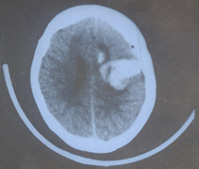

其他輔助檢查:CT或MRI可確定腦室擴大及程度及皮質萎縮的程度,有時可同時了解引起腦積水的原因。此外,CT或MRI還能了解腦積水是急性腦積水還是慢性腦積水,為臨床處理措施的套用提供依據。在腦積水的診斷中,應注意與腦萎縮引起的腦室擴大相區別,後者腦室擴大的同時可明顯地顯示出側裂或腦溝,甚至可有腦溝及腦裂的明顯擴大。另外診斷腦積水應儘可能明確是梗阻性腦積水還是交通性腦積水。

鑑別診斷:低級星形細胞瘤、腦室內囊腫,可通過MRI進行鑑別,也需要與局限性腦室擴大相鑑別。